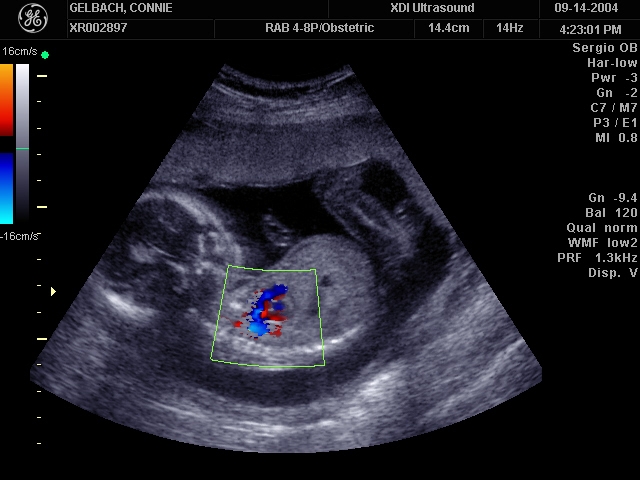

Sonograms